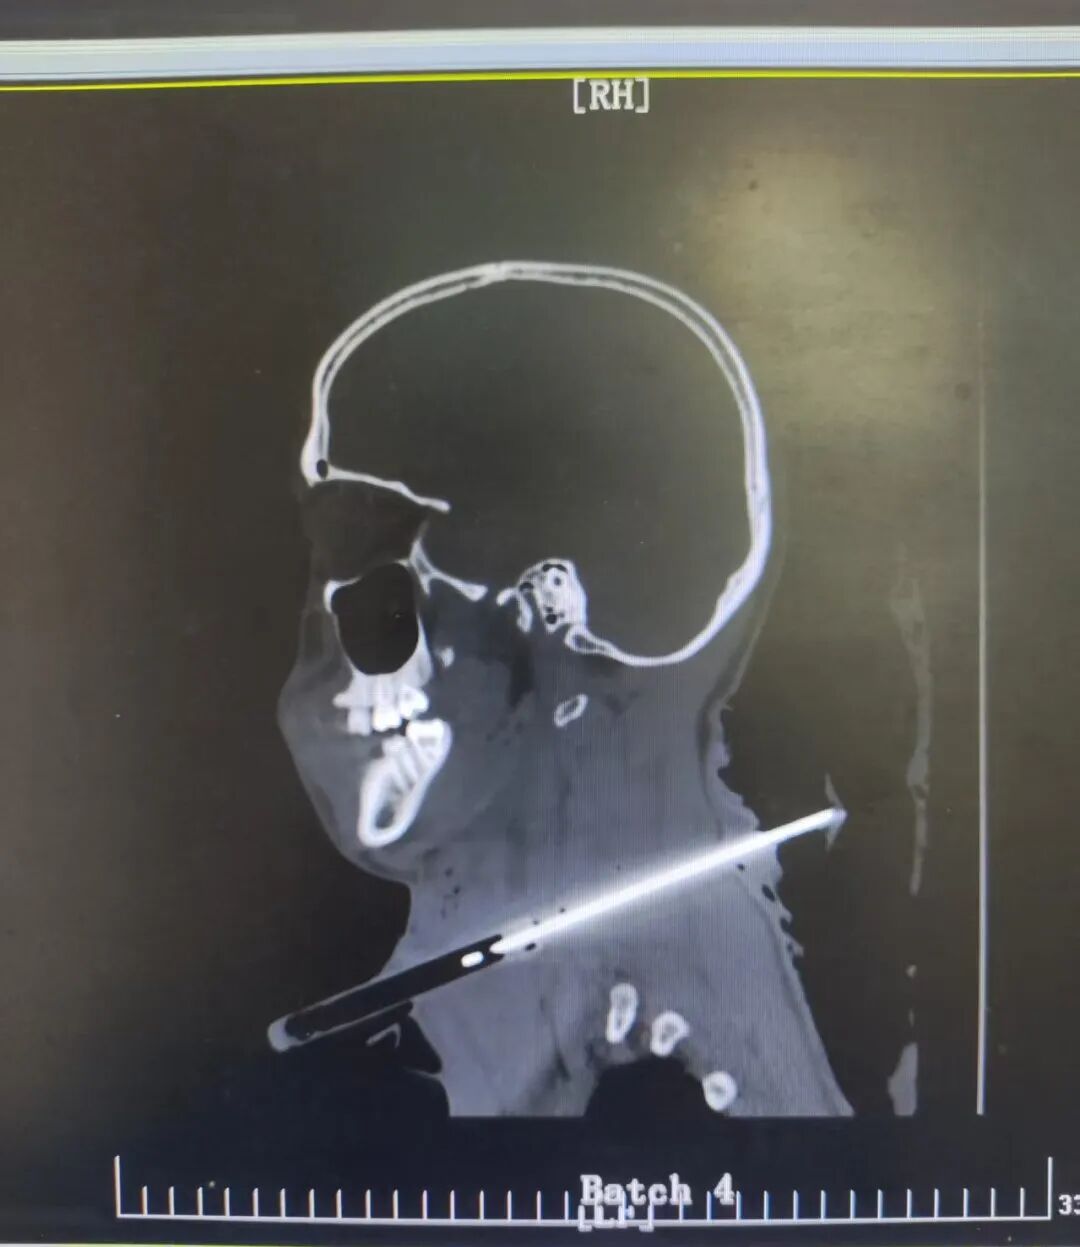

患者入院时CT

根据胃肠血管外科主任张善忠回忆,接诊时,患者颈部伤口鲜血呈喷射状涌出,面色惨白、意识模糊。CT提示:贯通伤通道紧贴右侧椎体前缘,一旦偏移毫厘,颈椎或脊髓损伤将直接导致截瘫;而颈总动脉的破裂,随时可能让患者在几分钟内因大出血死亡。